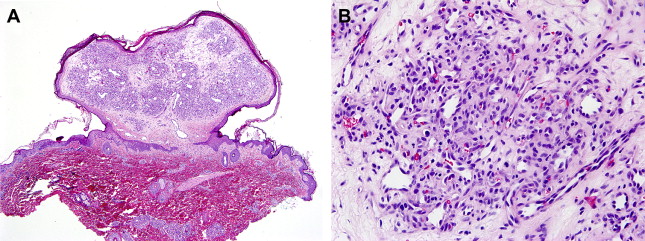

PG is a polypoid dermal lesion composed of lobules of curved capillaries and venules lined by plump endothelial cells ( Fig. 4 A). The individual capillaries and lobules are separated by edematous to fibrotic stroma with scattered inflammatory cells (see Fig. 4 B). The overlying epithelium may be atrophic and ulcerated and frequently shows lateral collarettes or indented hyperplastic surface epithelium encasing the lesion (see Fig. 4 A). A prominent feeding artery is often seen at the base of the lesion. If ulceration ensues, a rind of inflammatory granulation tissue may overlie the lesion. In the late stages, a decreased number of lobules is present and the stroma is more fibrotic. Some lesions are deep-seated and involve the reticular dermis or subcutaneous tissue only, and rarely PG may occur intravascularly. In the absence of epidermal changes, PGs may superficially resemble an infantile hemangioma, but the curved channels, intervascular stroma, and epidermal collarettes in PG are helpful distinguishing features, as is the patient’s age. If uncertainty exists, the GLUT1 immunostain will differentiate the two because PGs are negative.